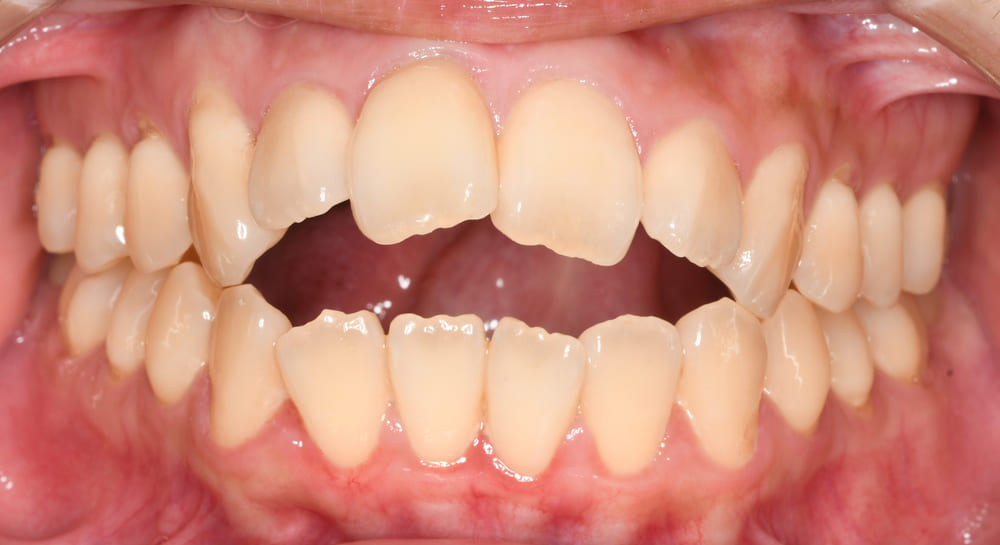

正面の口腔内写真では、前歯部の上下的な開き(開咬)が約10mmあり、通常の平均値(オーバーバイト:マイナス2〜3mm)と比べてかなり大きく開いている状態です。

右側の写真では、

という、典型的な開咬パターンが確認されました。

スマイル写真からも、舌を前方に押し出す「舌突出癖」が見られます。

この癖は治療期間の延長や後戻りのリスク要因となるため、患者さまにも十分に説明し、できるだけ癖をやめるように気にしながら生活するようにお伝えしました。